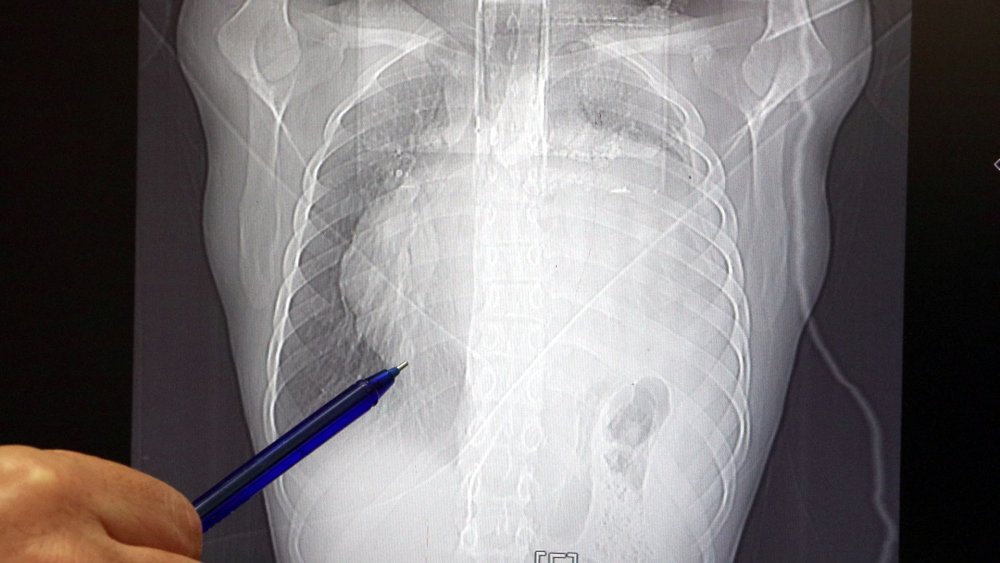

İstanbul'da yaşayan 21 yaşındaki Burak Aktaş, Temmuz ayında işe girmek üzere sağlık raporu almak için hastaneye gitti. Herşey yolundaydı ve raporunu alarak iş başı yaptı. Bir ay geçmeden nefes darlığı, halsizlik, öksürük gibi şikayetlerle başka bir hastaneye gittiğinde ise ilk şoku yaşadı. Sol göğüs boşluğunda portakal büyüklüğünde bir kitle tespit edilmişti. Yapılan biyopside tümörün akciğer kaynaklı olmadığı, henüz cenin aşamasında eşey hücrelerinin farklılaşmasıyla gelişen "immatür teratom" teşhisi kondu. Kitleyi küçültmek için kemoterapi uygulansa da tam tersine tümör 2 ay içinde neredeyse 10 katına çıktı ve büyük bir karpuz boyutuna ulaştı. Sol akciğerinin yüzde seksenini kağıt gibi ezen, kalbini göğüs duvarında 12 santim sağa kaydıran ve hem kalbe hem beyne giden ana damarlara baskı yapan 6.5 kilo ağırlığındaki dev tümör, Koşuyolu Yüksek İhtisas Eğitim ve Araştırma Hastanesi Göğüs ve Kalp Damar Cerrahisi ekiplerinin birlikte girdiği operasyonla başarılı şekilde çıkarıldı. Operasyon sırasında Aktaş'ın kalbi normal yerine çekildi, sol akciğerin üst lobu alındı, ezilen alt lobu ise anestezi ekipleri tarafından pozitif basınçla yeniden şişirildi. Ameliyatı gerçekleştiren ekipten Prof. Dr. Erdal Taşçı, Aktaş'ın göğüs boşluğunun neredeyse tamamını kaplayan 6,5 kiloluk tümörün teratom (eski Yunancada "canavar tümör') türlerinden biri olduğunu ve embriyonik hücrelerden kaynaklandığını kaydetti.

Prof. Dr. Erdal Taşçı, "Bundan 2,5-3 ay öncesine kadar hiçbir problemi olmayan, hayatını normal devam ettiren bir delikanlı Burak. Göğüs ağrısı öksürük ve nefes darlığı şikayetiyle sağlık kuruluşuna başvuruyor. Orada yapılan tetkiklerinde sol göğüs boşluğunda akciğerinden kaynaklanmayan portakal büyüklüğünde bir kitle tespit ediliyor ve immatür teratom tanısı konuyor. 2 ay arayla yapılan tetkiklerinde ve arada cerrahi öncesi küçültme amaçlı kemoterapi almasına rağmen, portakal büyüklüğündeki tümör, irice bir karpuz büyüklüğüne, yaklaşık 6 kilo 300 grama kadar ulaşıyor. Göğüs boşluğunda kemik kafesi içinde olduğu için, itebileceği iki organ var; biri kalp, diğeri de akciğerler. Soldan sağa doğru büyüdüğü için kalbi tamamen göğüs boşluğunun sağ tarafına itmiş ve kalbe giren ve kalpten çıkan bütün büyük damarları da yer değiştirmenin etkisiyle bükülmüş durumdaydı. Bu nedenle vücuduna yeterince kan gitmiyordu. Ağustos ayının başında portakal büyüklüğündeyken kitle Eylül sonuna irice bir kavun, Ekim ayına geldiğimizde ise bir karpuz büyüklüğüne ulaştığı için, kitlenin büyüme hızı bizi acilen ameliyat yapmaya yöneltti. Yaklaşık 8-10 kat hacimsel olarak artmıştı. Sol akciğer tamamen ezilmiş ve kağıt haldeydi, alt lobu anestezi ekibimiz yüksek basınç uygulayarak tekrar şişirdi. Çok fazla vaktimiz yoktu, kitle basısından dolayı yaşamla bağdaşmayacağından dolayı hızlı hareket etmek zorundaydık. Bize geldikten üç gün sonra hemen ameliyata aldık çünkü tümörden ziyade onun yaptığı baskıdan kaynaklı hayati riski vardı" dedi.